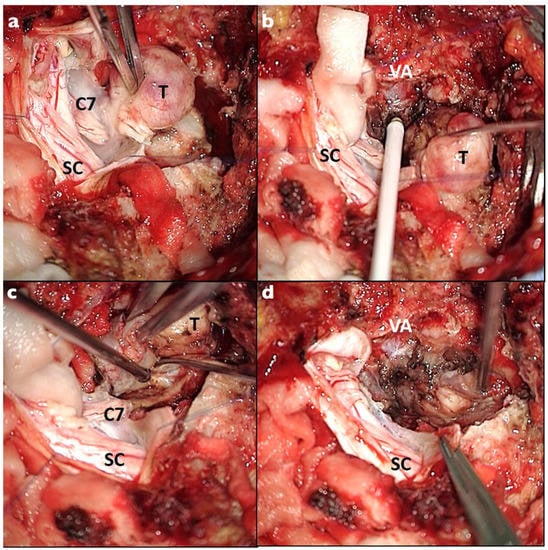

Figure 2. Intraoperative photos of the C7 foraminal dumbbell schwannoma. A posterior midline approach and two-level laminectomy were performed: (a) the lesion was dissected from the spinal cord (SC); the C7 root was identified and completely sacrificed; (b) the lesion was mobilized thanks to the nerve resection and the vertebral artery (VA) was identified using the intraoperative doppler; (c,d) dissection of the extraforaminal part and “en bloc” resection of the lesion was performed.

Careful dissection of the surrounding nerve rootlets and roots was performed in order to identify and sacrifice exclusively the parent spinal root. Once the parent nerve root was identified, complete resection was performed at the most distal and proximal point at the junction between the lesion and the nerve (Figure 1 and Figure 2). The intracanal and foraminal part was successfully resected in all cases. GTR resection was achieved in 22 patients (84.6%) and was obtained with a complete en bloc resection in 18 cases (69.2%). Four patients (15.4%) with a huge paraspinal component (3 Sridhar grade IVB and 1 grade V) had STR. The residual part was paravertebral in all cases. No second-stage surgery was considered necessary in these cases according to the clinical context, and no progression was observed at follow-up. Surgical complications occurred in four (15.4%) patients: two CSF leaks and two wound infections. All required surgical management. The mean postoperative follow-up was 22.4 months (range 6–85 months). No recurrence was observed.